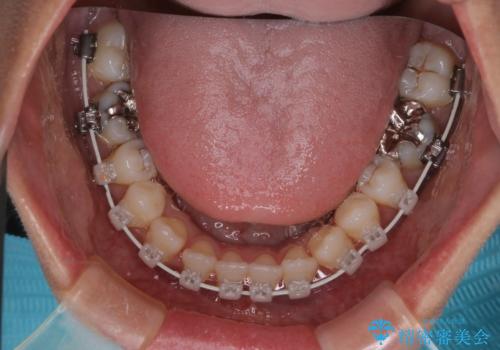

- 開咬を主訴に来院されました。前歯部に開咬、右側大臼歯部にクロスバイトが認められます。ワイヤー矯正の審美装置で治療し、ゴム掛けを行いながら噛み合わせを改善しました。

主訴である開咬と右側大臼歯部クロスバイトを改善でき、しっかりと噛むことができるようになりました。